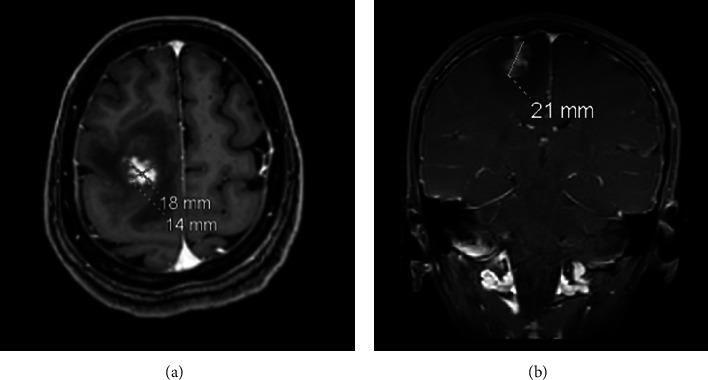

Schistosomiasis is a parasitic infection caused by schistosome invasion of blood circulation. Neuroschistosomiasis is a severe cerebral complication that accounts for less than 2.3% of reported cases. Patients present with progressive encephalitis, seizures, or both. Management includes antiparasitic medications, steroids, and surgical intervention. . We report a case of a 44-year-old female who presented to the ER with a history of transient loss of consciousness (LOC) and seizure. Radiological investigations revealed a right frontal brain lesion. Histopathological results confirmed the diagnosis of schistosomiasis.

血吸虫病是由血吸虫侵入血液循环引起的寄生虫感染。神经血吸虫病是一种严重的脑部并发症,在报告病例中占比不到2.3%。患者表现为进行性脑炎、癫痫发作或两者皆有。治疗包括抗寄生虫药物、类固醇和手术干预。我们报告一例44岁女性病例,该患者因短暂意识丧失(LOC)和癫痫发作史就诊于急诊室。影像学检查发现右侧额叶脑部病变。组织病理学结果确诊为血吸虫病。